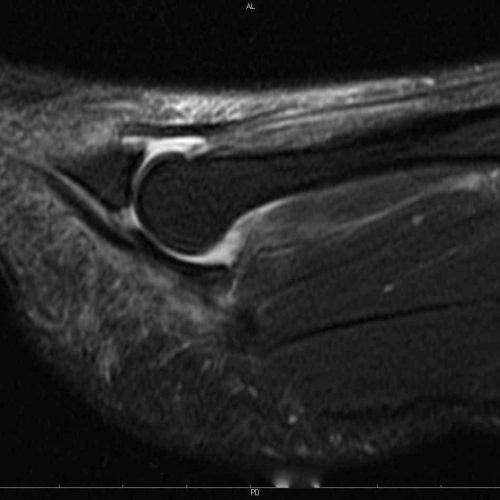

Corredor com historia de dor e inchaço no antepé, mais precisamente na região plantar da articulação entre o 2o metatarso e a falange proximal.

Ressonância magnética do antepé com identificação de rotura da placa plantar metatarsofalângica do 2o dedo, junto a inserção lateral e sinovite articular.